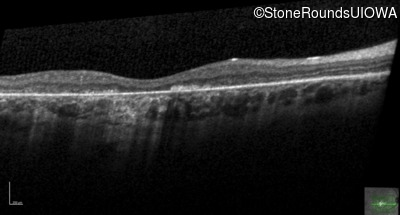

Optical Coherence Tomography - Left - 10/125

Exemplar / OCT Stack

OCT Stack